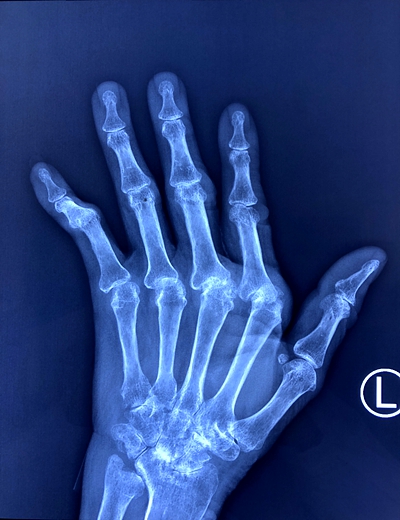

多关节半脱位,部分关节融合,骨质疏松

游运辉教授带领的团队对聂女士进行了检查,发现:类风湿关节炎很明确,现在是重度活动时期。长时间的不规范治疗,使得聂女士已经出现多个小关节的畸形、功能障碍,肺部也受到累及,发生了间质性改变。关节的畸形不能再恢复,肺部的病变以后也有再进一步进展,出现呼吸困难的可能,目前需要积极治疗。